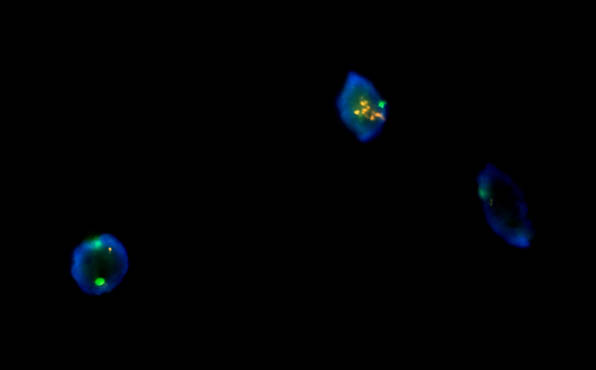

FISH荧光原位杂交产品目前在国内主要有三大领域:实体瘤、血液病和产前/流产诊断。实体瘤和血液病在医院开展FISH检测较多,与靶向药物治疗相关的一些探针观察,如乳腺癌HER-2等。产前/流产诊断,主要是染色体数目异常或结构异常。如此次北京某公司需要的荧光显微镜对试剂FISH样品进行检测

此次,工程师推荐的全套FISH荧光显微镜整套方案包含成像软件和相机,成像清晰,操作简便,检测快速,24小时内出结果,且结果易观察,并且重复性好,空间定位准确。标本来源丰富:间期细胞、分裂中期细胞、分化或者未分化细胞以及死亡或者存活的细胞都可以被检测